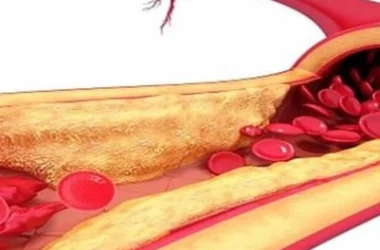

محفزات التهاب الكلى

السبب الرئيسي لالتهاب الكلية هو انتقال العدوى البكتيرية من المثانة إلى الكلى. غالبًا ما تكون هذه العدوى ناتجة عن بكتيريا الإشريكية القولونية (E. coli). في حالات نادرة، قد تنتقل العدوى من الدم إلى الكلى. تعتبر النساء أكثر عرضة للإصابة بالتهاب الكلية بسبب قصر مجرى البول لديهن مقارنة بالرجال، مما يسهل انتقال البكتيريا إلى المثانة والكلى. بالإضافة إلى ذلك، تكون النساء الحوامل أكثر عرضة للإصابة بالتهاب الكلية نتيجة لضغط الجنين على الحالب، مما يعيق تدفق البول بشكل طبيعي.